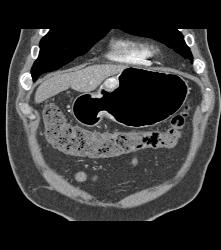

GIST Tumor